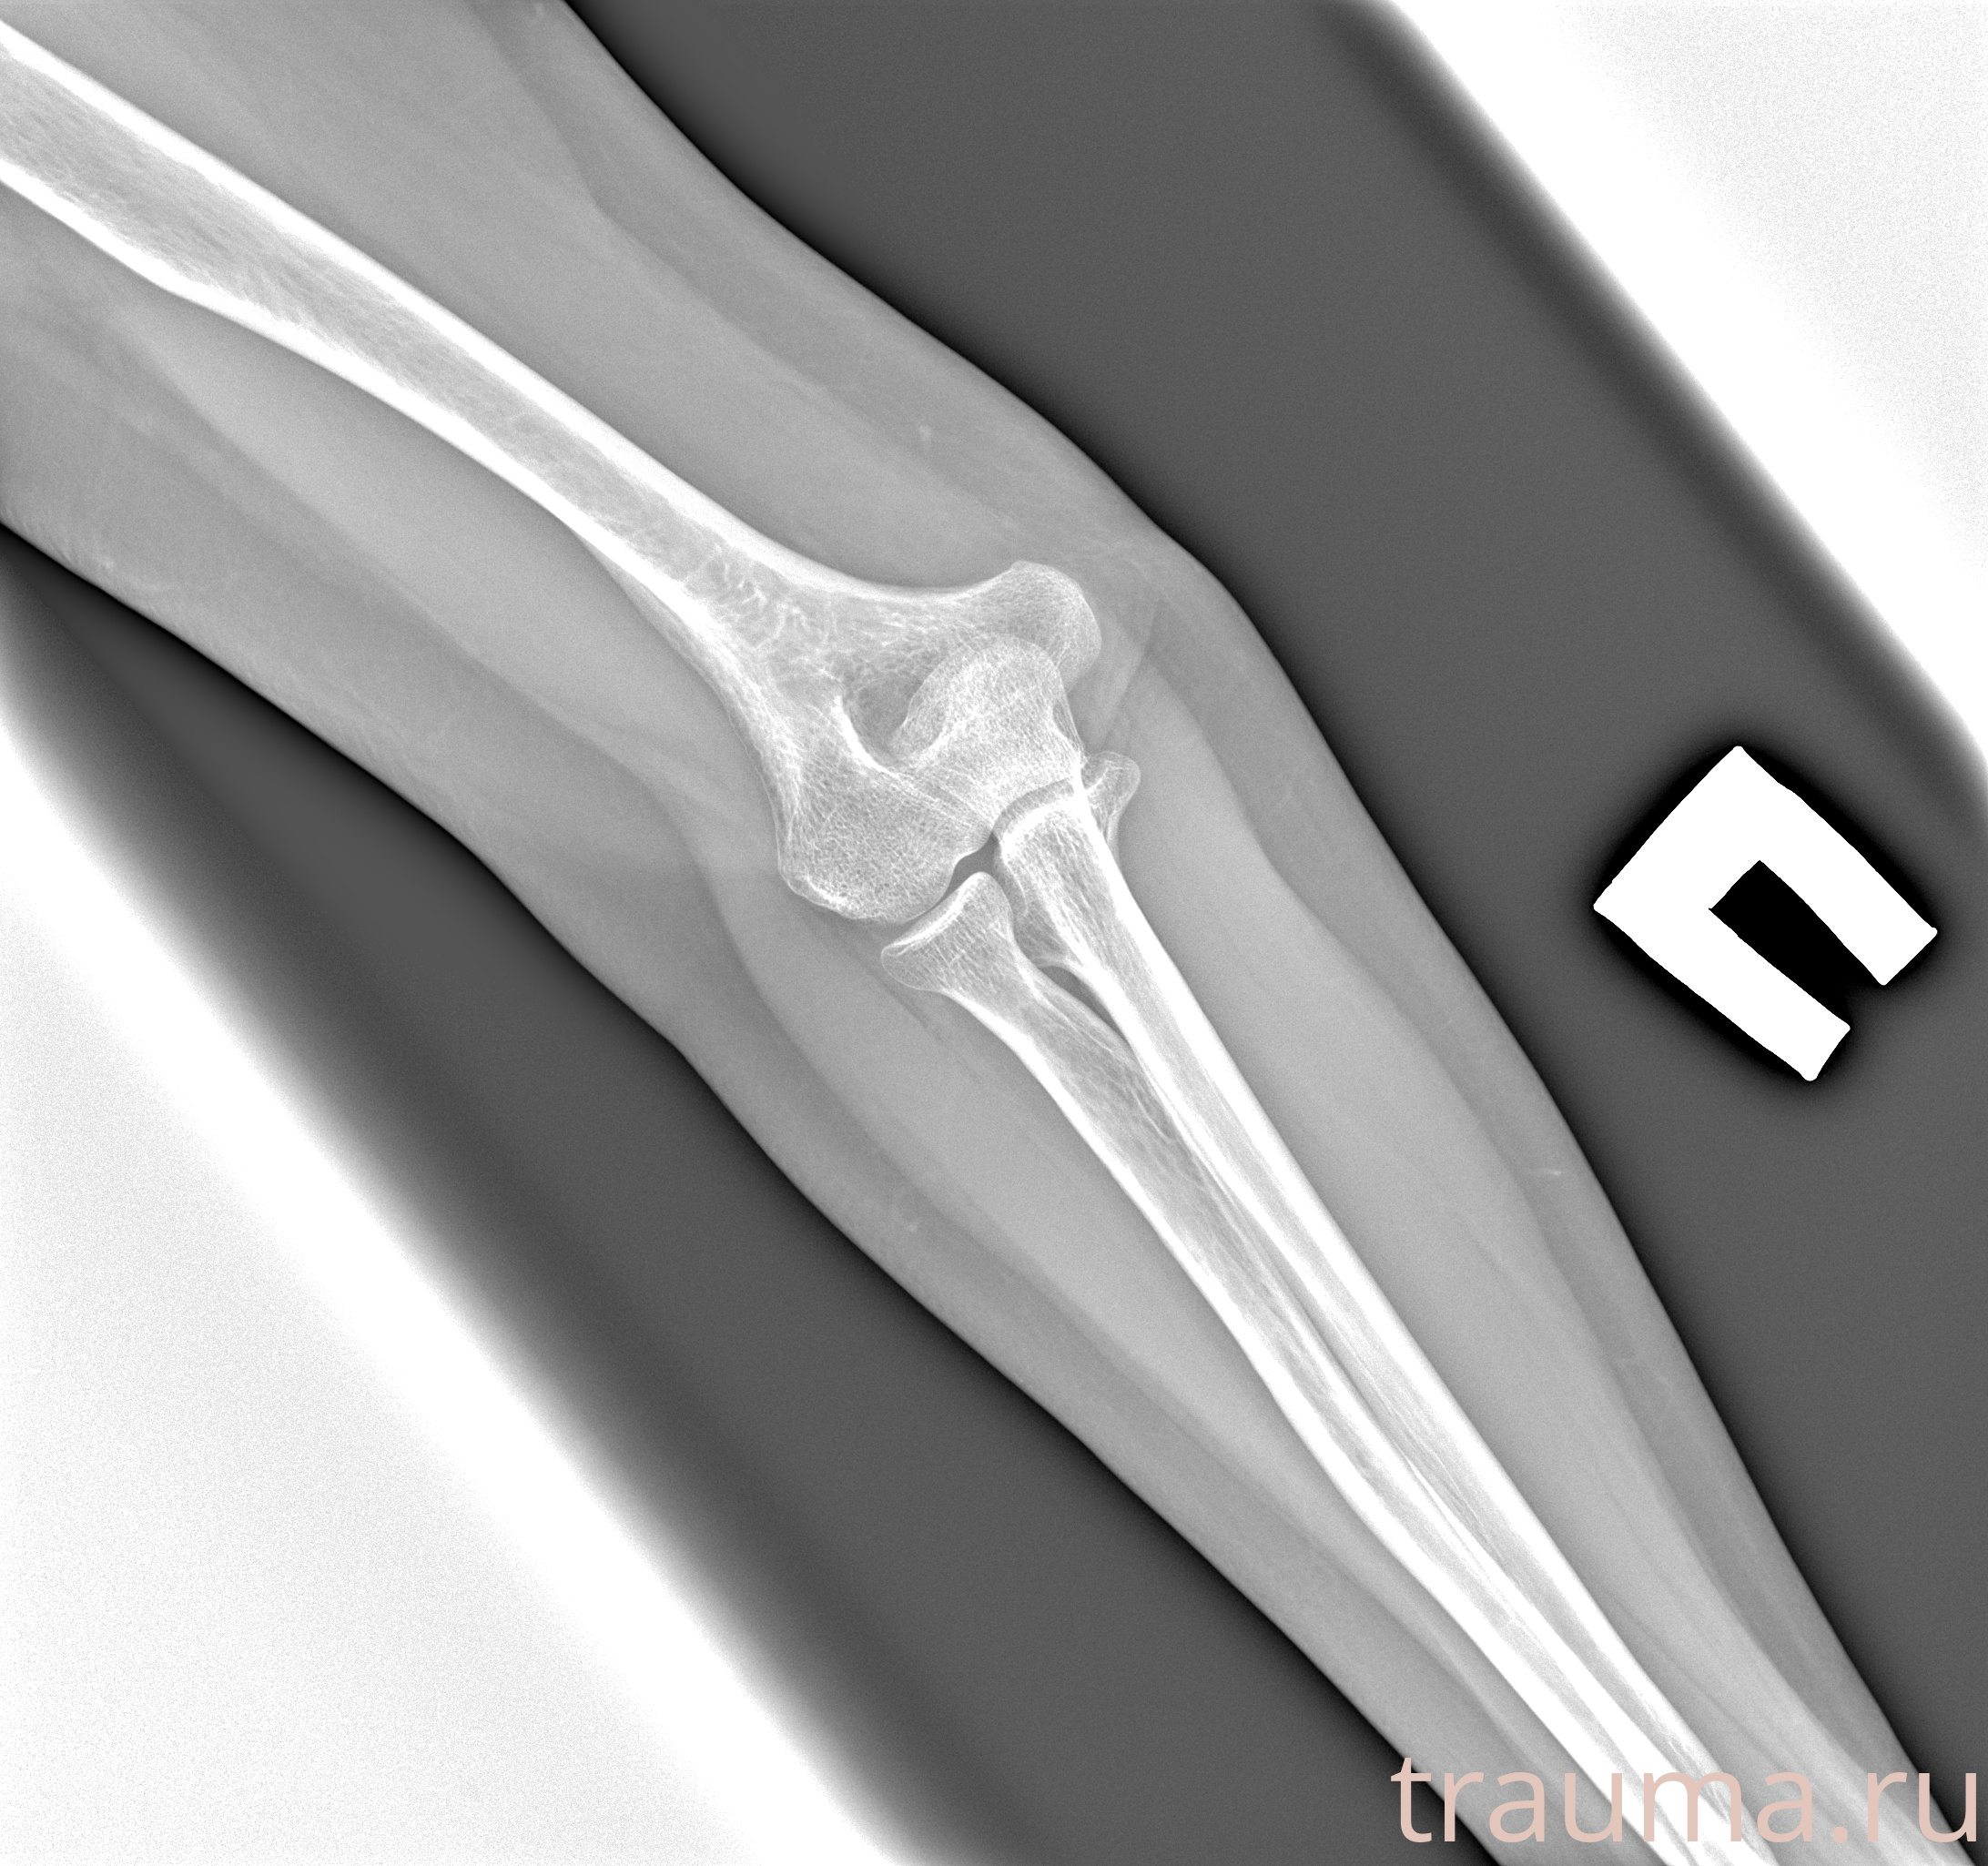

Рентгенограммы

Рентген на дому: по вашему адресу приезжает врач-рентгенолог, травматолог-ортопед с мобильным рентгеновским аппаратом, проводит диагностику травмы или заболевания, делает необходимые рентгенограммы, дает рекомендации по дальнейшему лечению. Получить качественные снимки в домашних условиях возможно благодаря уникальной методике, разработанной МосРентген Центром для института  Склифосовского